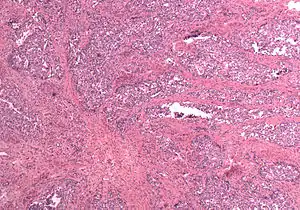

In gross appearance, MMMTs are fleshier than adenocarcinomas, may be bulky and polypoid, and sometimes protrude through the cervical os. On histology, the tumors consist of adenocarcinoma (endometrioid, serous or clear cell) mixed with the malignant mesenchymal (sarcoma) elements; alternatively, the tumor may contain two distinct and separate epithelial and mesenchymal components. Sarcomatous components may also mimic extrauterine tissues (e.g., striated muscle, cartilage, adipose tissue, and bone). Metastases usually contain only epithelial components.